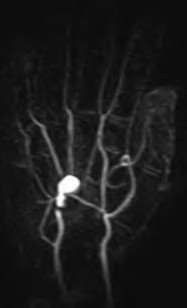

Contrast enhanced MRA of the wrist is typically used to diagnose hypothenar hammer syndrome or other vascular abnormalities.